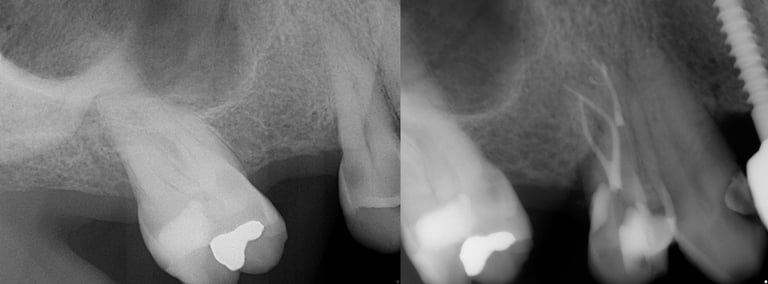

Gallery 3: Surgical Cases

Surgical Root Canal Cases (Apicoectomy) with preoperative and postoperative radiographs.

#3 Sx MB Root

#13 Sx